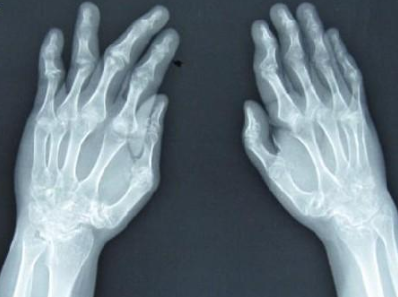

河南内风湿关节炎医院介绍到类风湿关节炎又称为类风湿,是以慢性对称性多关节炎和关节外病…[详情]

河南治疗内风湿专科医院介绍到类风湿关节炎引起的原因目前并不是非常清楚,它是由于各种炎…[详情]